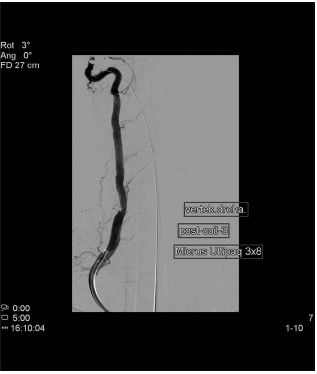

Con el diagnóstico de fistula arteriovenosa directa de alto flujo de localización vertebro-vertebral en el segmento V2 derecho con sobrecarga de las venas del plexo periraquídeo vertebral cervical y drenaje final en la vena yugular interna, se programo para tratamiento endovascular. Este se realizó dos días más tarde bajo anestesia general, accediendo por vía femoral para cateterismo selectivo de la arteria vertebral derecha y embolización mediante espirales de platino con oclusión completa de la fístula sin complicaciones. A las 24 horas la enferma refirió la desaparición del soplo y el resto de la sintomatología, permaneciendo hasta la actualidad asintomática.